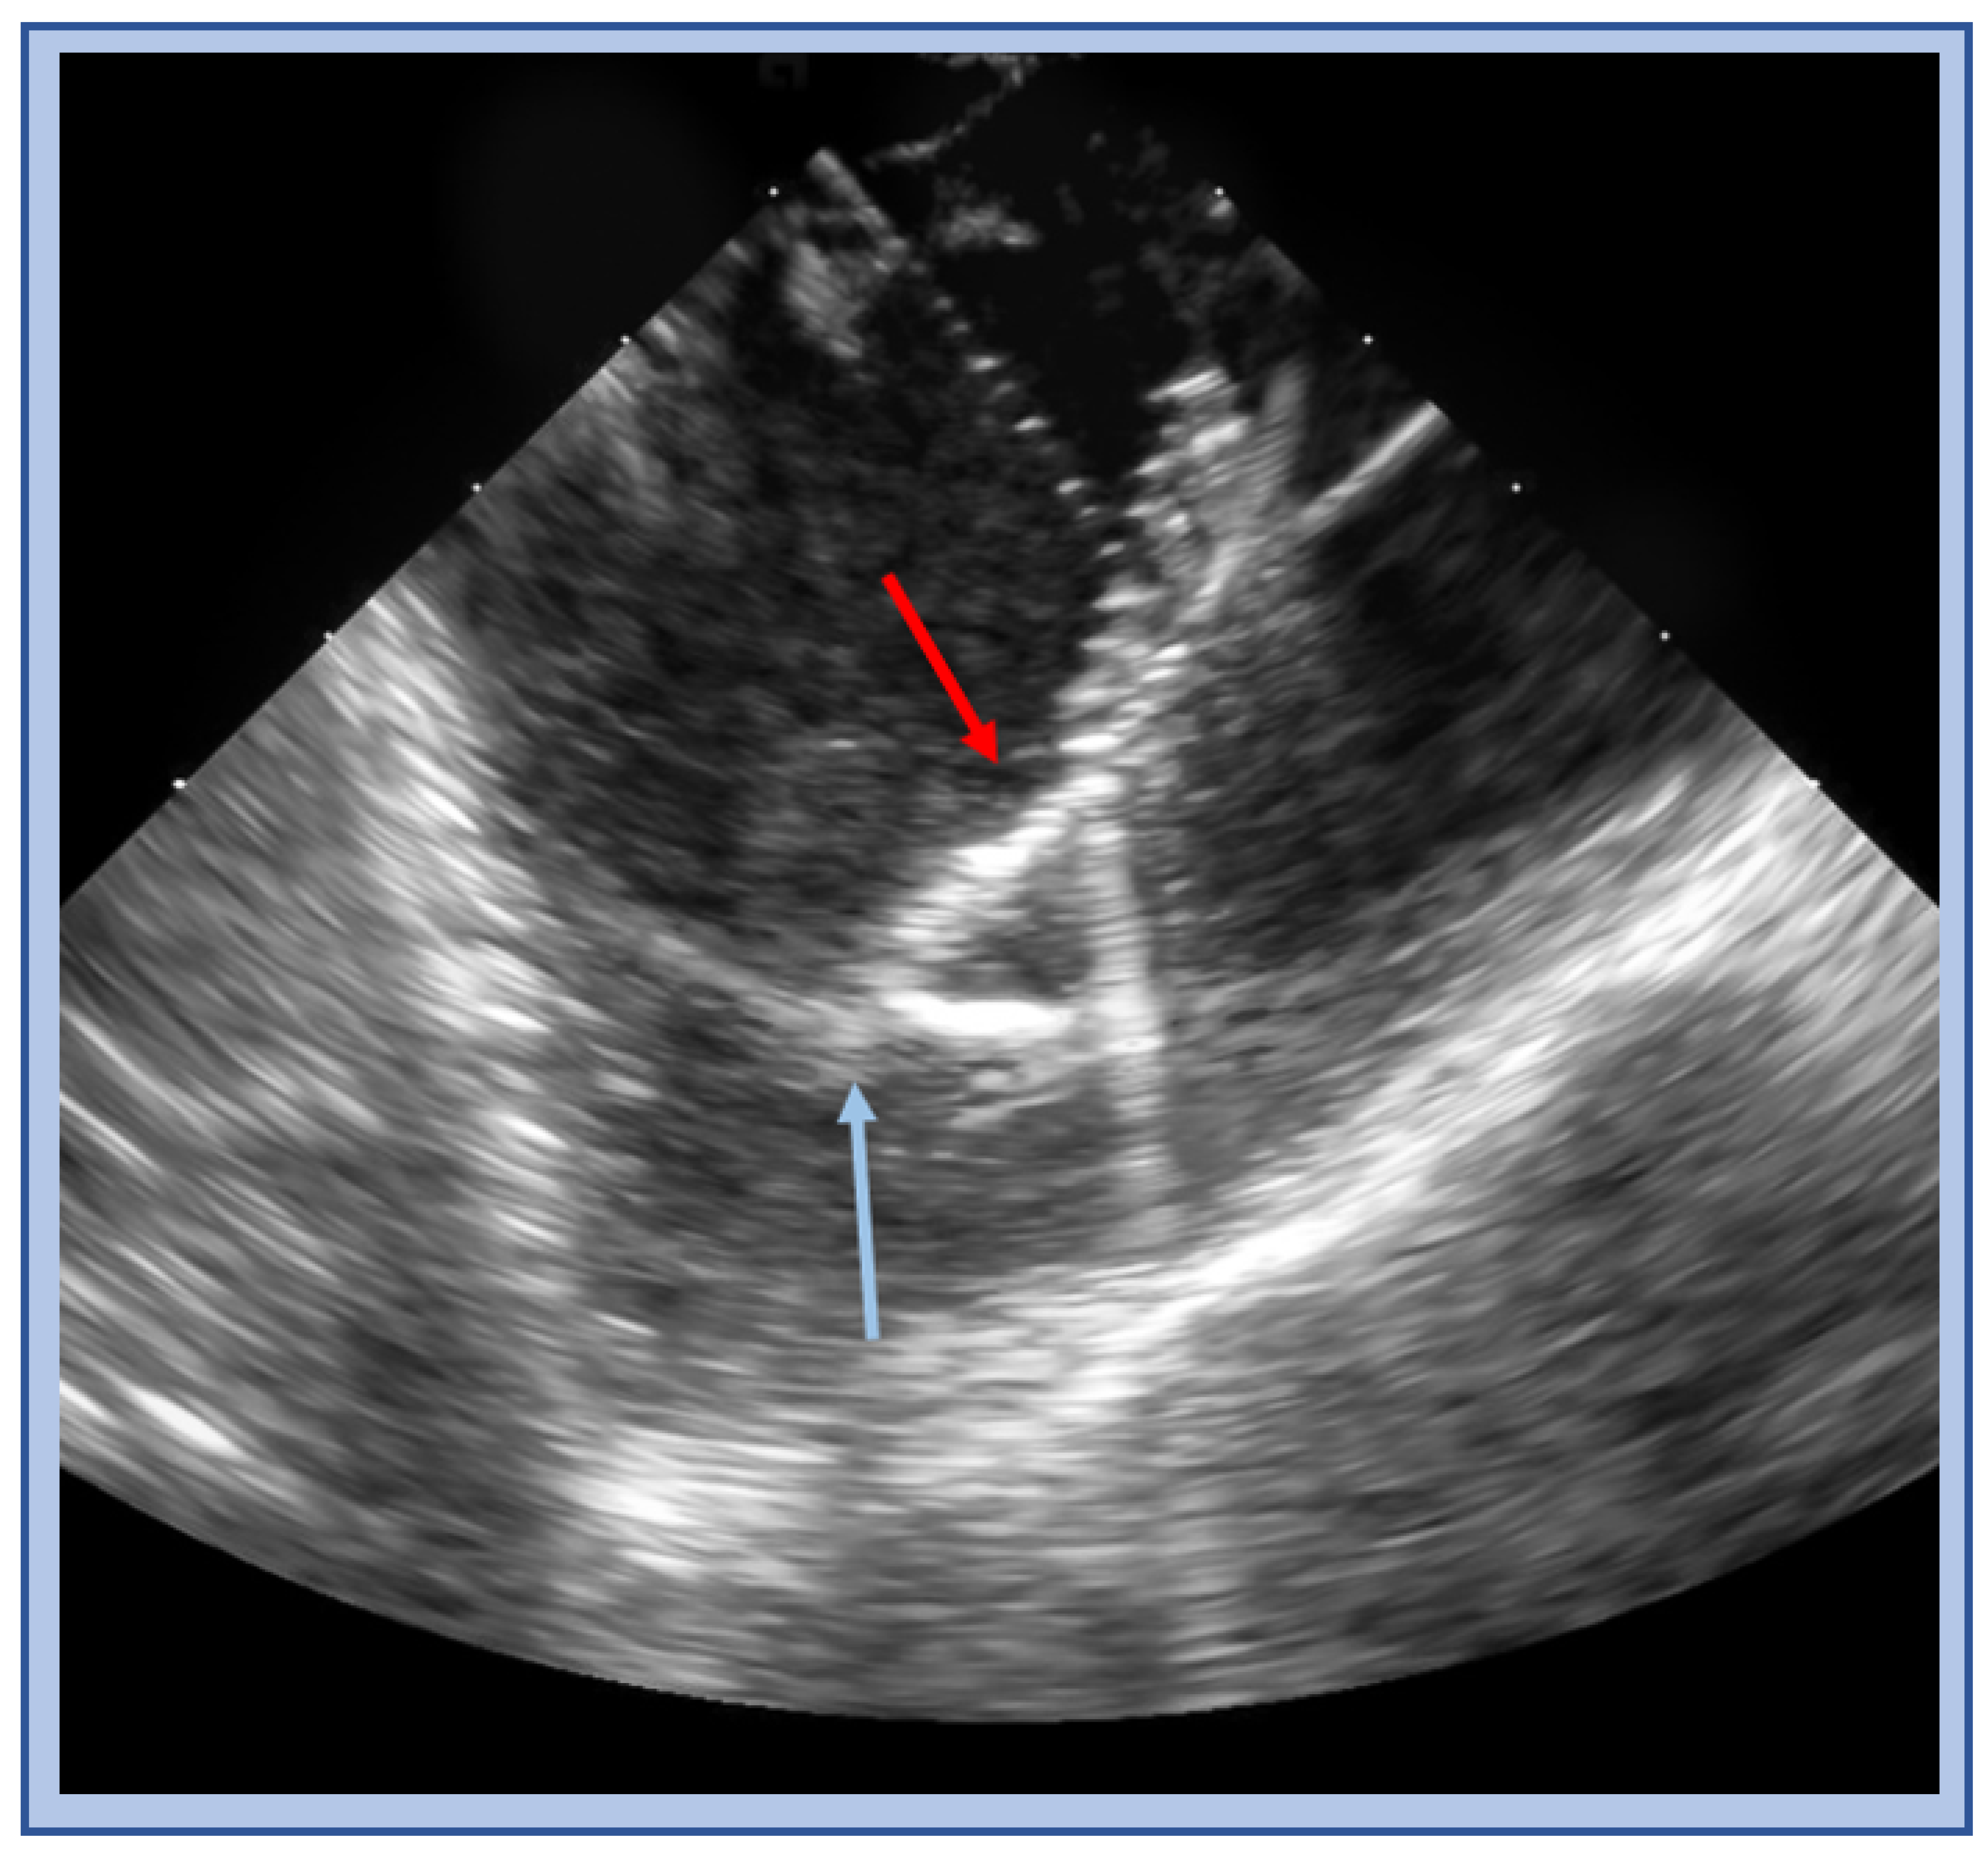

5. Papillary Muscle VT

5.2. Catheter Ablation Considerations